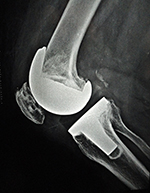

OA - CASE 2

Imm psop ap

Imm psop lt

Imm psop